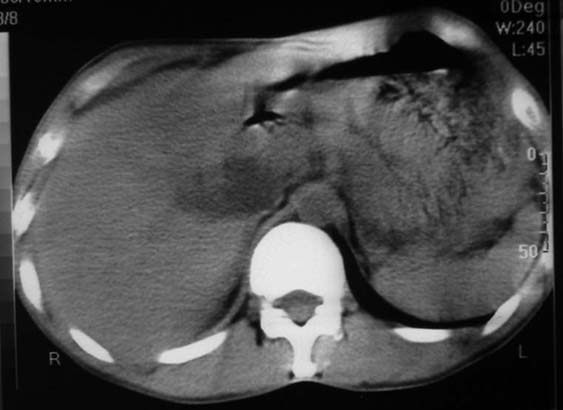

男,50y,右上腹包块痛10天,查:右上腹饱满,右肋下触及6*6cm大小包块,质硬,压痛。患者诉:10天前感冒胸闷,痛,后痛及右上腹部,既往有肝炎病史。

没有增强!只能考虑左叶内侧段巨块型肝癌(外生型)可能性大;胆囊呢?不除外胆囊癌累及肝脏。

病变位于胆囊窝内,其内密度不均,肝总管及胆总管扩张,胃里面没有清水充盈,不解为什么楼主不做好了准备再做呢,支持:“左叶内侧段巨块型肝癌(外生型)可能性大;不除外胆囊癌累及肝脏”建议增强吧。

左叶内侧段巨块型肝癌(外生型)可能性大

首先考虑左叶内侧段巨块型肝癌(外生型),建议c+